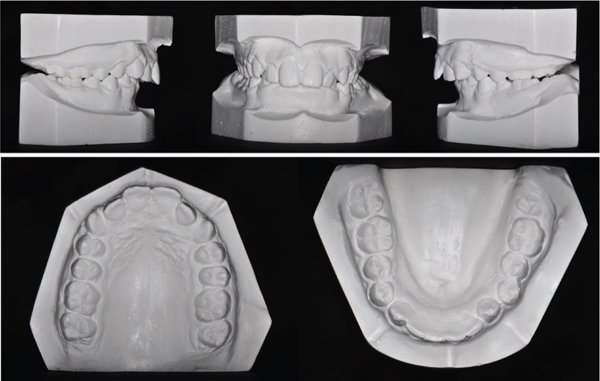

Dysharmonie dento-maxillaire (DDM)

Sans extraction

- DDM faible/transitoire (≤ 4 mm) : Stripping des dents temporaires (Van der Linden, 1990) :

- DDM modérée (4-7 mm) :

Avec extraction

- DDM sévère (> 7-8 mm) :

- S’abstenir en denture mixte et traiter en denture permanente avec extractions.

- Ou pratiquer des extractions programmées.